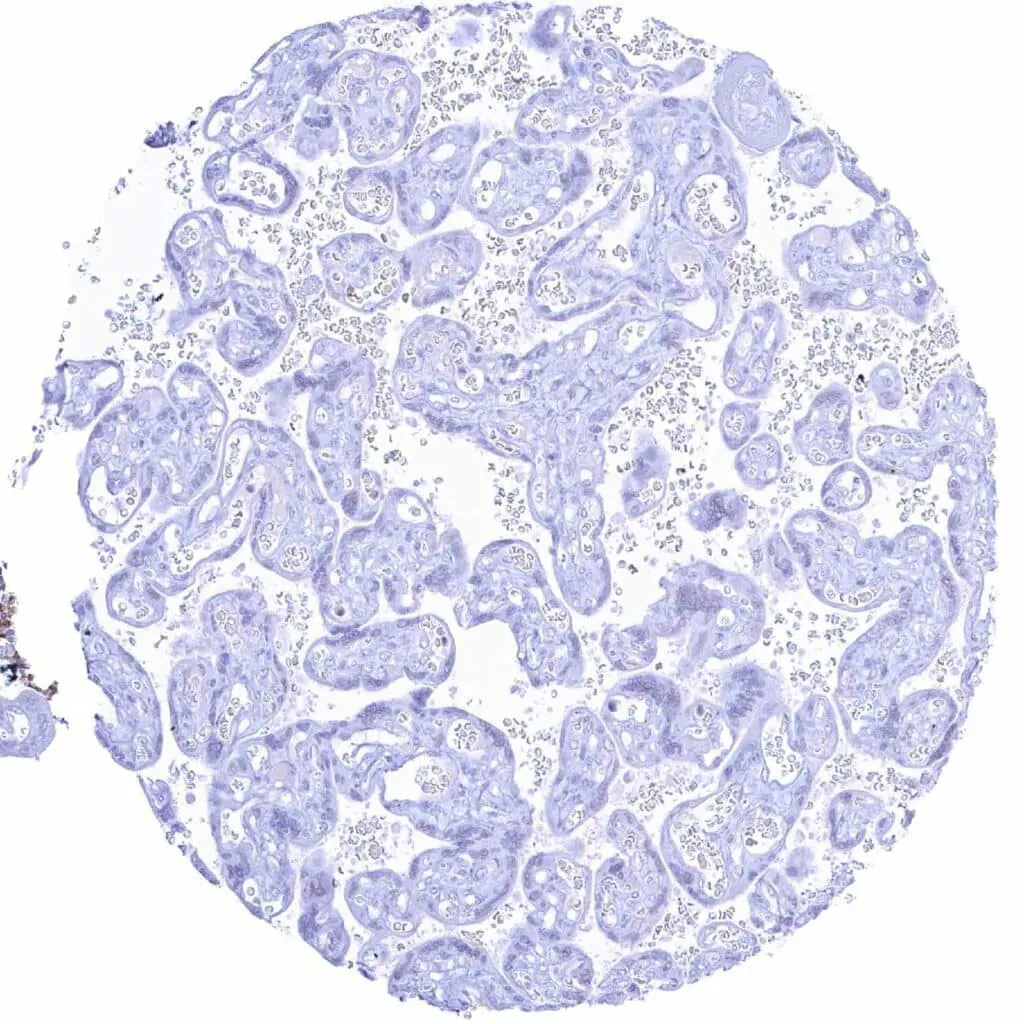

Placenta (amnion and chorion)

Placenta, early

Placenta, mature